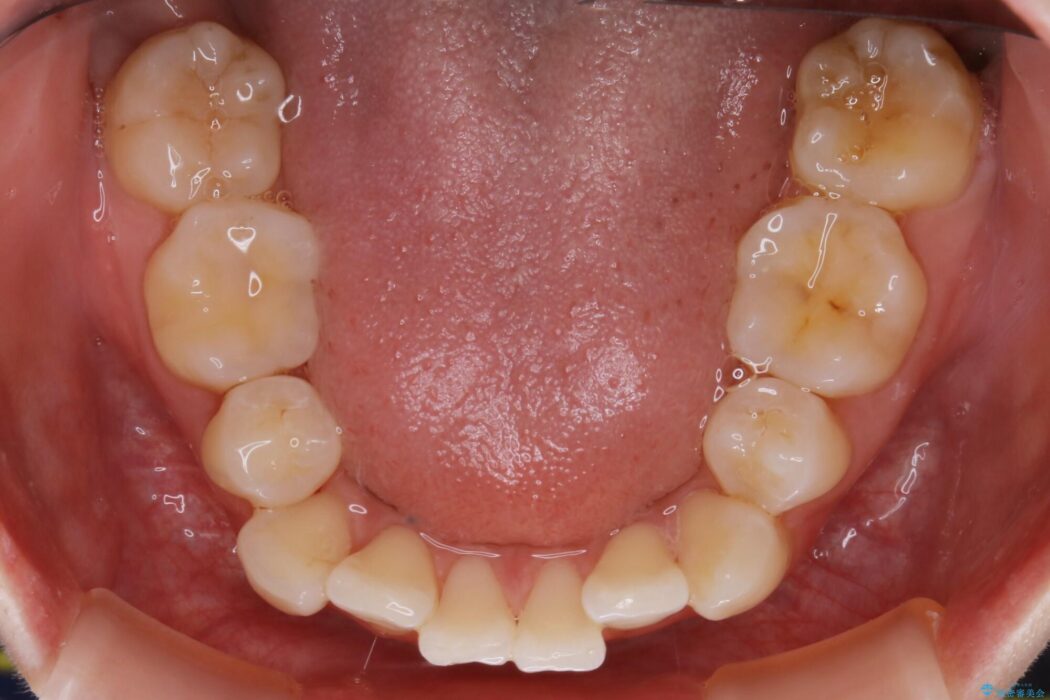

以前治療した抜歯矯正から後戻りをしてしまった歯列のがたつきを再矯正したいとのことで来院されました。

元々中学生から高校生にかけてワイヤー装置を用いた矯正治療をされた患者様でした。

大人になるにつれてライフスタイルの変化が生じ、歯が元の位置に戻らないように保定するためのリテーナーを継続使用することが難しくなったことから、歯列にがたつきが目立つようになったのでもう一度矯正治療をしたいとのご希望でした。

既に上下左右の4番目の歯が抜歯されているため、今回のケースでは非抜歯による歯の移動のみで矯正をしなければならず、難易度が高いものになりました。